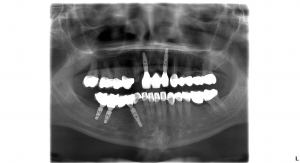

Natália túžila mať dokonalé zuby a dokonalý úsmev. Rozhodla sa podstúpiť radikálnu zmenu. Jej ošetrenie zahŕňalo dve extrakcie, päť zubných implantátov, sedem implantových koruniek, pätnásť celokeramických koruniek, päť kovokeramických koruniek.